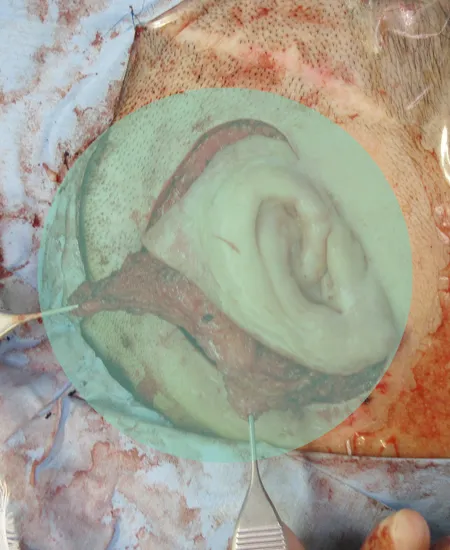

STEP 03

新たに肋軟骨を採取し肋軟骨ブロックを作成しました。

剥離した耳の後面に新たに肋軟骨ブロックを挿入し周囲の動脈弁などでくるみます。